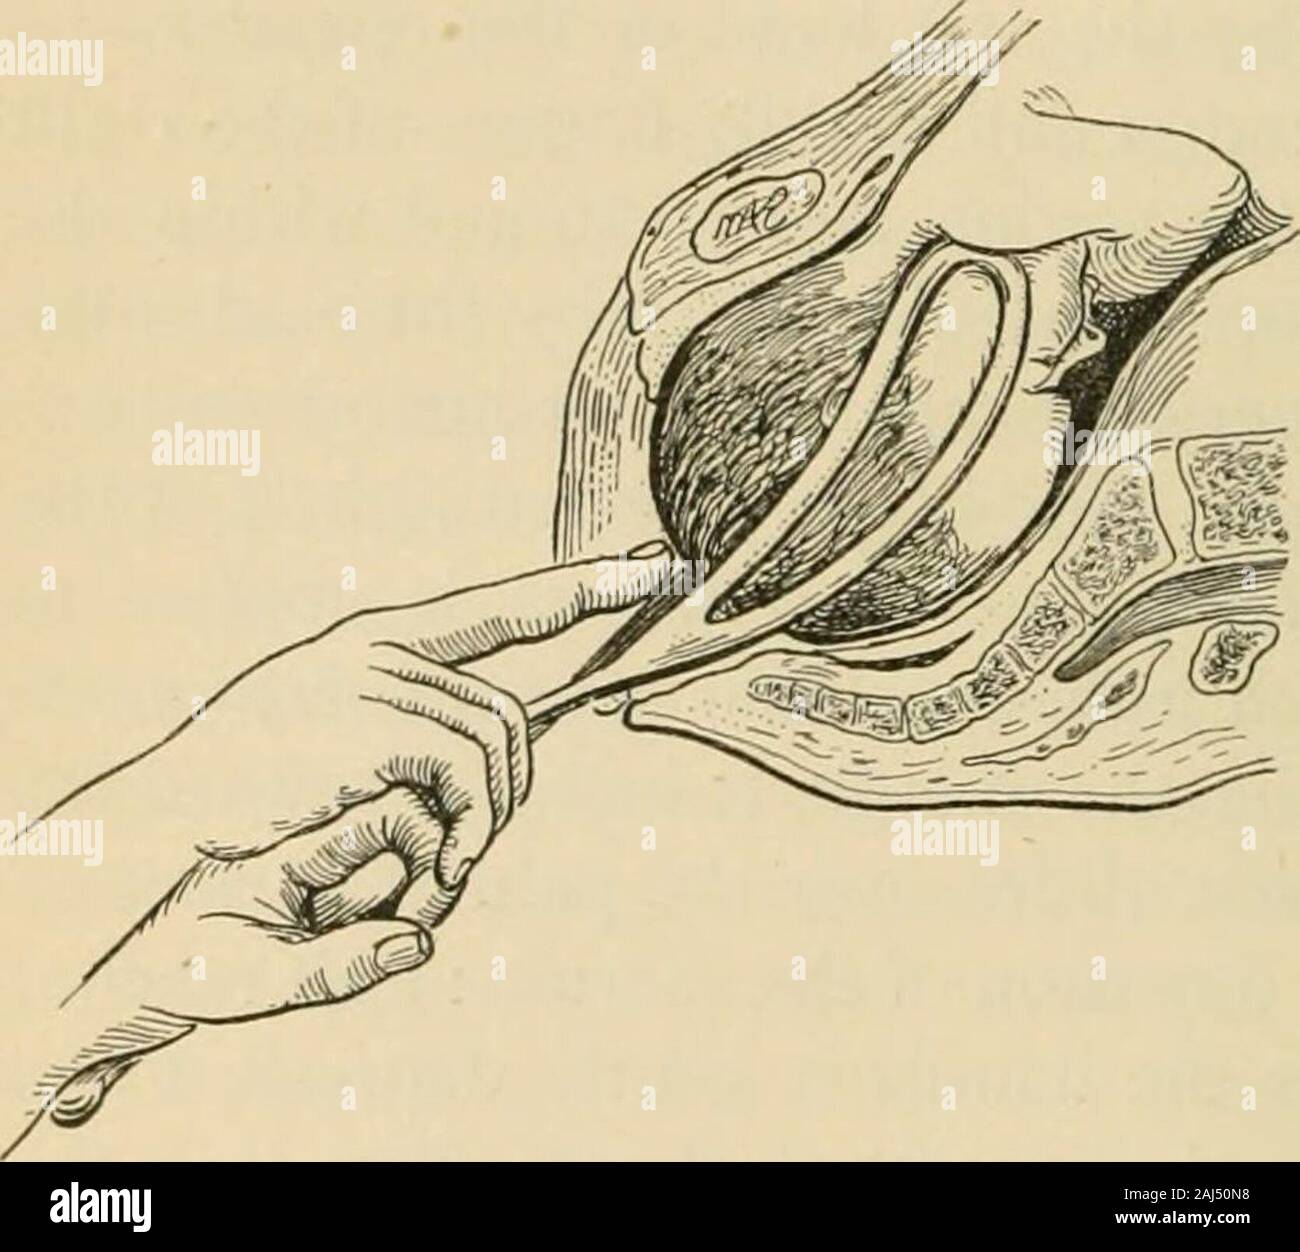

This is the two positions of an infant while in the uterus. copyright 1844 Stock Photohttps://www.alamy.com/image-license-details/?v=1https://www.alamy.com/stock-photo-this-is-the-two-positions-of-an-infant-while-in-the-uterus-copyright-37139594.html

This is the two positions of an infant while in the uterus. copyright 1844 Stock Photohttps://www.alamy.com/image-license-details/?v=1https://www.alamy.com/stock-photo-this-is-the-two-positions-of-an-infant-while-in-the-uterus-copyright-37139594.htmlRFC4BRX2–This is the two positions of an infant while in the uterus. copyright 1844

The practice of obstetrics, designed for the use of students and practitioners of medicine . t fronto-anterior and -posterior—the left hand is the one to use in-ternally for grasping the foot or feet, as this hand most naturally by the shortestpath and with least disturbance of the fetal ellipse comes to the feet and readilyselects one or both for traction. However, in right dorso positions—namely, inright occipito-anterior and -posterior, in left mento-anterior and -posterior, andin left fronto-anterior and -posterior—the righthand should be used, for the above reasons.In pelves flattened fro Stock Photohttps://www.alamy.com/image-license-details/?v=1https://www.alamy.com/the-practice-of-obstetrics-designed-for-the-use-of-students-and-practitioners-of-medicine-t-fronto-anterior-and-posteriorthe-left-hand-is-the-one-to-use-in-ternally-for-grasping-the-foot-or-feet-as-this-hand-most-naturally-by-the-shortestpath-and-with-least-disturbance-of-the-fetal-ellipse-comes-to-the-feet-and-readilyselects-one-or-both-for-traction-however-in-right-dorso-positionsnamely-inright-occipito-anterior-and-posterior-in-left-mento-anterior-and-posterior-andin-left-fronto-anterior-and-posteriorthe-righthand-should-be-used-for-the-above-reasonsin-pelves-flattened-fro-image343043188.html

The practice of obstetrics, designed for the use of students and practitioners of medicine . t fronto-anterior and -posterior—the left hand is the one to use in-ternally for grasping the foot or feet, as this hand most naturally by the shortestpath and with least disturbance of the fetal ellipse comes to the feet and readilyselects one or both for traction. However, in right dorso positions—namely, inright occipito-anterior and -posterior, in left mento-anterior and -posterior, andin left fronto-anterior and -posterior—the righthand should be used, for the above reasons.In pelves flattened fro Stock Photohttps://www.alamy.com/image-license-details/?v=1https://www.alamy.com/the-practice-of-obstetrics-designed-for-the-use-of-students-and-practitioners-of-medicine-t-fronto-anterior-and-posteriorthe-left-hand-is-the-one-to-use-in-ternally-for-grasping-the-foot-or-feet-as-this-hand-most-naturally-by-the-shortestpath-and-with-least-disturbance-of-the-fetal-ellipse-comes-to-the-feet-and-readilyselects-one-or-both-for-traction-however-in-right-dorso-positionsnamely-inright-occipito-anterior-and-posterior-in-left-mento-anterior-and-posterior-andin-left-fronto-anterior-and-posteriorthe-righthand-should-be-used-for-the-above-reasonsin-pelves-flattened-fro-image343043188.htmlRM2AX2Y2C–The practice of obstetrics, designed for the use of students and practitioners of medicine . t fronto-anterior and -posterior—the left hand is the one to use in-ternally for grasping the foot or feet, as this hand most naturally by the shortestpath and with least disturbance of the fetal ellipse comes to the feet and readilyselects one or both for traction. However, in right dorso positions—namely, inright occipito-anterior and -posterior, in left mento-anterior and -posterior, andin left fronto-anterior and -posterior—the righthand should be used, for the above reasons.In pelves flattened fro